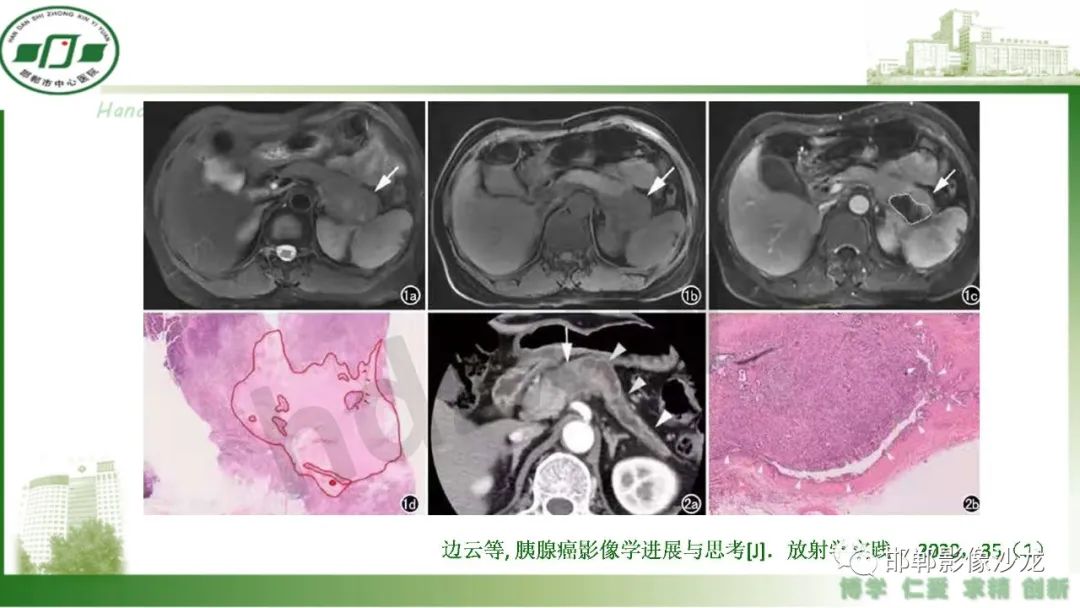

肿块性胰腺炎与胰腺癌的临床、实验室检查、影像学表现有时候很难鉴别,但两者的临床处理、预后又有很大的不同,因此我们平时工作中需要注意两者之间的区别,谨慎诊断,力争为患者及临床带来更大的帮助。